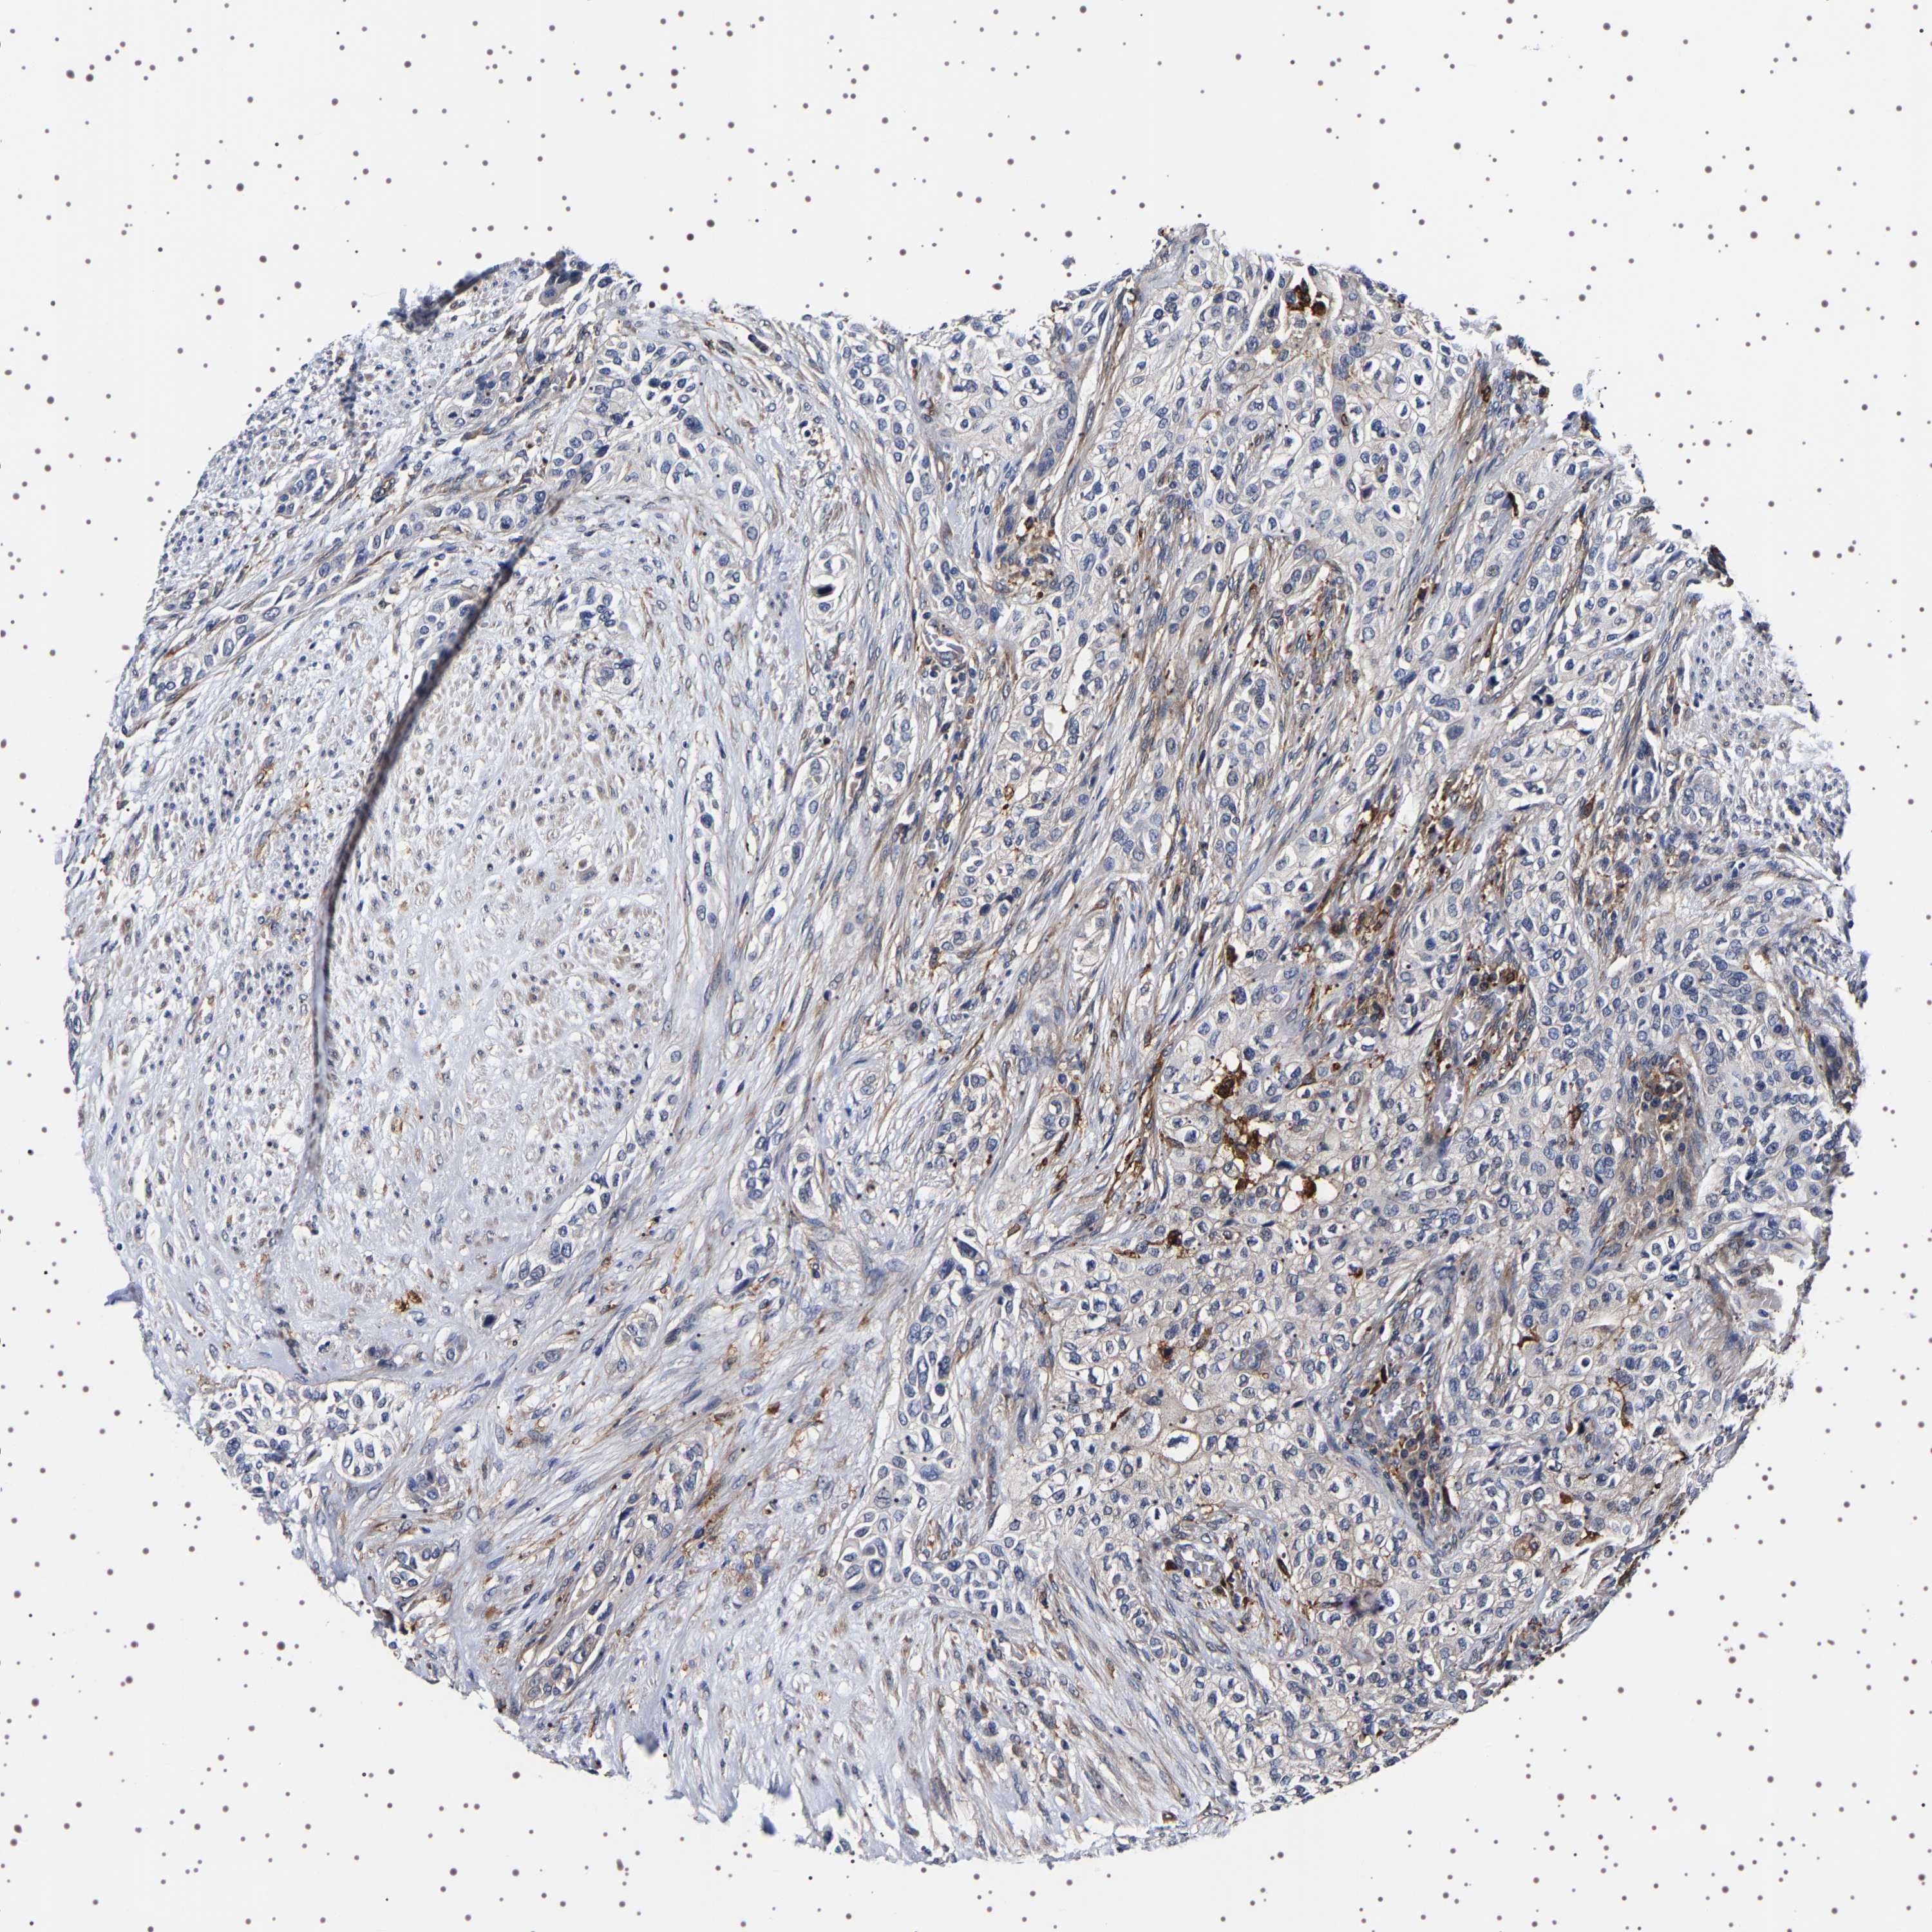

UROTHELIAL CANCER - Protein expressioni

A mouse-over function shows sample information and annotation data. Click on an image to view it in a full screen mode. Samples can be filtered based on level of antibody staining by selecting one or several of the following categories: high, medium, low and not detected. The assay and annotation is described here.

Note that samples used for immunohistochemistry by the Human Protein Atlas do not correspond to samples in the TCGA dataset.

Antibody stainingi

Antibody staining in the annotated cell types in the current human tissue is reported as not detected, low, medium, or high, based on conventional immunohistochemistry profiling in selected tissues. This score is based on the combination of the staining intensity and fraction of stained cells.

Each image is clickable and will lead to virtual microscopy that enables deeper exploration of all samples and also displays staining intensity scores, fraction scores and subcellular localization as well as patient and tissue information for each sample.

Antibody HPA007105

Antibody HPA008765

Antibody CAB020829

Staining

High

Medium

Low

Not detected

Intensity

Strong

Moderate

Weak

Negative

Quantity

>75%

75%-25%

<25%

None

Location

Nuclear

Cytoplasmic/membranous

Cytoplasmic/membranous,nuclear

Urothelial carcinoma, Low grade

Urothelial carcinoma, High grade